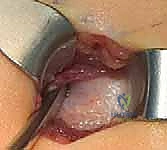

بدلاً من فتح الساق بالكامل، يقوم الدكتور هطيف بعمل ثقوب صغيرة جداً (مليمترات) في الجلد. باستخدام أدوات دقيقة جداً (مثل الإزميل الدقيق أو المثقاب المتخصص)، يتم قطع العظم في أماكن التقوس من الداخل دون إتلاف الأنسجة الرخوة أو العضلات المحيطة. هذا يحافظ على التروية الدموية للعظم (Periosteum)، مما يسرع من التئام العظم بشكل مذهل.

الخطوة الرابعة: إدخال المسمار التلسكوبي

بعد تقويم العظم وجعله مستقيماً كحبات المسبحة على خيط، يتم إدخال السلك الدليلي (Guide Wire). ثم يتم إدخال الجزء الخارجي (الأنثوي) من المسمار التلسكوبي وتثبيته في الجزء العلوي من العظم (Epiphysis).

بعد ذلك، يتم إدخال الجزء الداخلي (الذكري) من المسمار عبر الجزء السفلي من العظم وتثبيته في المشاشة السفلية. هذا التصميم العبقري يضمن حماية العظم بالكامل من الداخل.